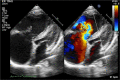

Figures